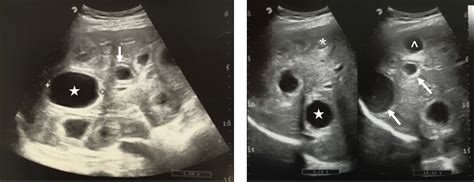

A liver ultrasound cyst is a fluid-filled sac that develops within the liver. These cysts can vary in size and number and are often discovered incidentally during routine imaging tests. Liver cysts can be classified into two main types: simple cysts and complex cysts. Simple cysts are benign and typically do not cause symptoms, while complex cysts may require further investigation due to the potential for malignancy.

• Genetic Factors: Certain genetic conditions, such as polycystic liver disease, can predispose individuals to developing multiple liver cysts.

The diagnosis of liver ultrasound cysts typically involves a combination of imaging tests and clinical evaluation. The primary diagnostic tool is the liver ultrasound, which provides detailed images of the liver and surrounding tissues. Additional tests may include:

• hepatic cyst ultrasound images

• simple cyst liver ultrasound